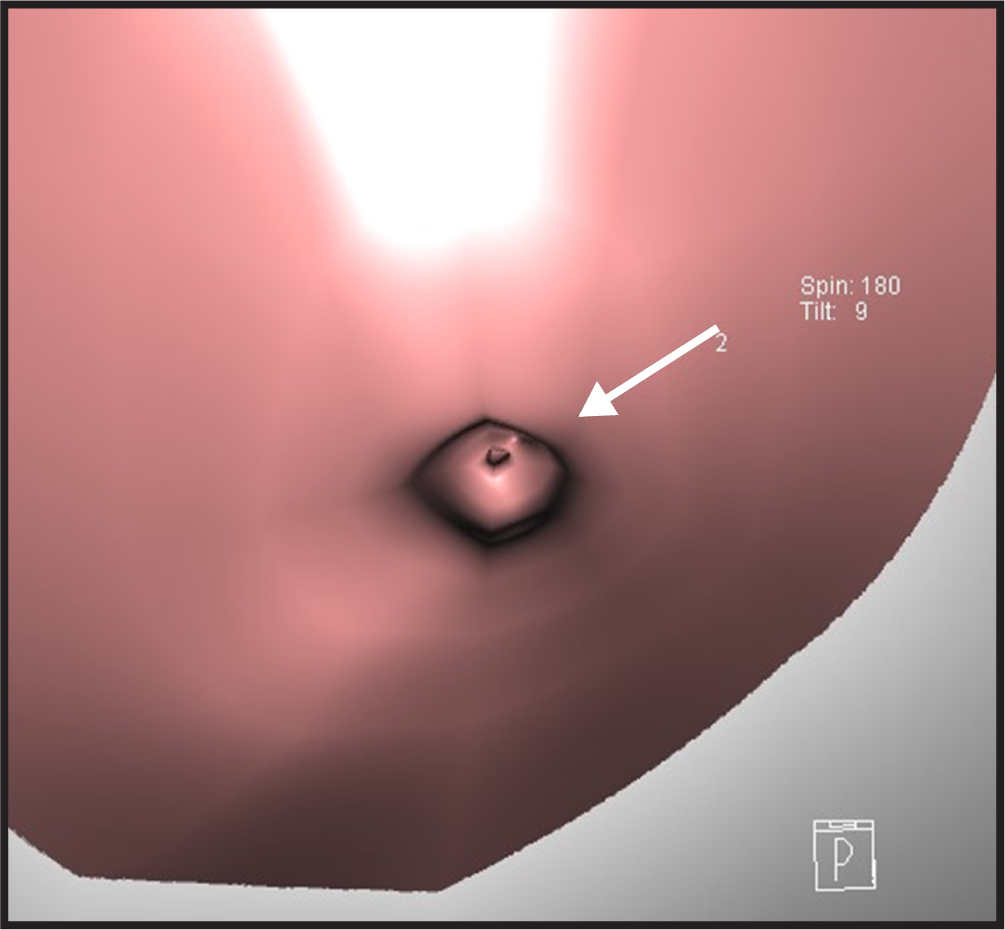

Virtual endoscopy was performed with CT-galactography images to obtain intracavity images of the discharging lactiferous ducts. Typical images of the polypoid-solitary (Fig. 1), polypoid-multiple (Fig. 2), superficial (Fig. 3), and combined type (Fig. 4) were obtained. The polypoid-multiple type was the most common type, followed by the combined type, whereas the superficial type was the rarest type. Table 2 presents the ultrasonography, mammography, and CT-G VE results of the benign, high-risk, and malignant lesions. Statistical analysis revealed histopathological correlations of the ultrasonography, galactography, and CT-G VE results.

Fig. 2.

Fig. 2.Exemplary computed tomography-galactography virtual endoscopy (CT-G VE) images of the polypoid-multiple type (A, B, and C).

Fig. 4.

Fig. 4.Exemplary computed tomography-galactography virtual endoscopy (CT-G VE) image of the combined type.